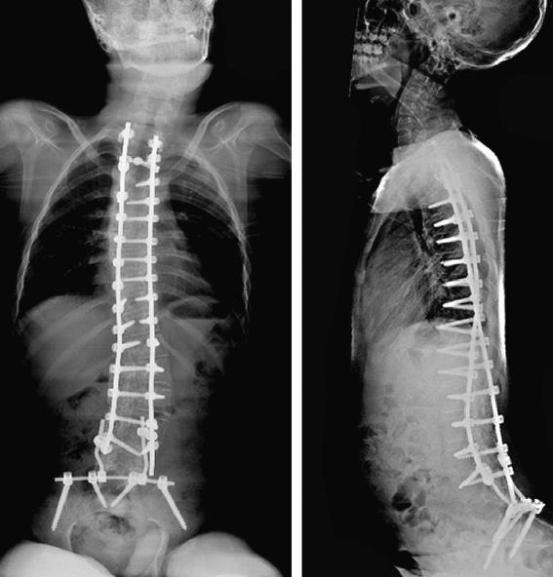

Sotos syndrome, CP, severe scoliosis

Neuromuscular scoliosis: Case 1

• August 2020

Hospitalizaton due to the presence of a dorsal fluid collection and elevated inflammatory markers.

MRI: posterior cervicodorsal abscess extending from the skin to the level of the spinal fixation

screw September 2020 surgical revision

• May 2021

Re evaluation with orthopedic surgeon.